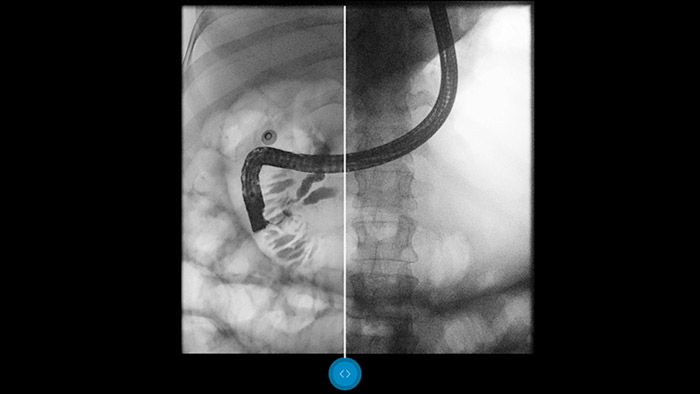

Compare imágenes en paralelo con un procesamiento de imágenes convencional y compruebe las ventajas por sí mismo.